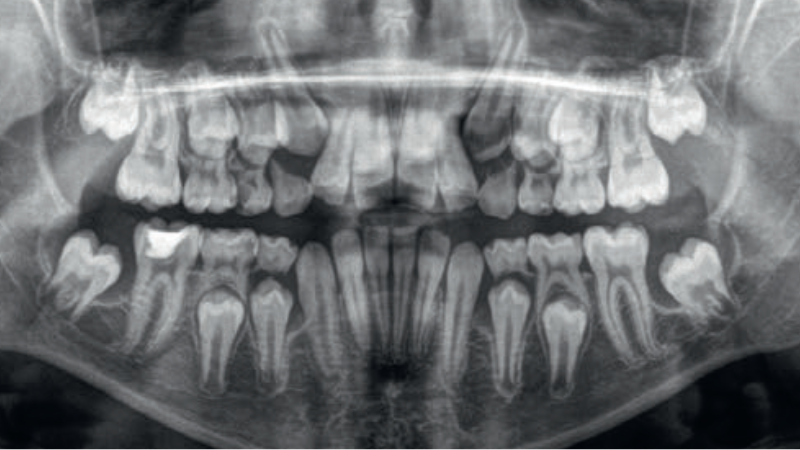

Streszczenie: Radiologia stomatologiczna odgrywa kluczową rolę w diagnostyce i planowaniu leczenia zaburzeń wyrzynania zębów. Szczególne znaczenie ma radiologiczna ocena drugich zębów trzonowych, której celem jest przewidywanie zaburzeń wyrzynania oraz zapobieganie wadom zgryzu i innym powikłaniom klinicznym. Materiał badawczy do artykułu stanowiły pantomogramy wykonane w gabinecie autorek w ciągu ostatnich 10 lat, obejmujące wyłącznie pacjentów powyżej 10. roku życia z nieprawidłowościami zatrzymanych drugich zębów trzonowych, przy jednoczesnym wykluczeniu radiogramów okołowierzchołkowych. Zaburzenia wyrzynania zębów trzonowych, w tym torbiele erupcyjne i przemieszczenia siódemek, stanowią istotny problem kliniczny. Ektopowe położenie zawiązków drugich zębów trzonowych, często związane z migracją trzecich trzonowców, jest rzadką, trudną diagnostycznie anomalią wymagającą wykonania CBCT, wczesnego rozpoznania [...]